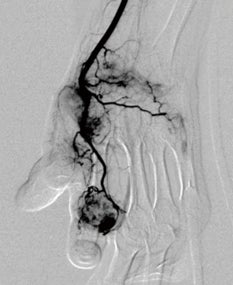

日常生活の中で、打撲や捻挫、繰り返しの動作(オーバーユース)などにより、気づかないうちに炎症が蓄積しています。若いときは、こうした小さな炎症は自然に治ります。しかし、加齢により消えるはずの不要な新生血管「モヤモヤ血管」が残ることで問題が生じます。

消えなかったモヤモヤ血管の増加とともに痛みを伝える神経も増えるため、そこから常に痛みの信号が脳へ送られます。その結果、長引く慢性的な痛み(慢性疼痛)を引き起こします。

痛みの原因であるモヤモヤ血管は、レントゲンやMRIでは写りません。湿布や痛み止めなどの対症療法では根本的に治せないため、原因である異常血管=モヤモヤ血管そのものを治療する必要があります。

モヤモヤ血管の治療法について

オクノクリニック総院長の奥野祐次医学博士(Yuji Okuno, MD, PhD)は、2013年に、炎症の原因となる異常血管に着目し、それを治療する新技術を開発「運動器カテーテル治療(TAME:Transcatheter Arterial Embolization for Musculoskeletal Disorders)」を世界で初めて論文として発表しました。

その治療法は、メスを使わず身体への負担が少ない低侵襲治療で、鼠蹊部から極細のカテーテルを挿入し、モヤモヤ血管に薬剤を注入して炎症を鎮めます。治療時間は約20分、入院の必要もなく絆創膏で止血できる日帰り治療として注目されています。